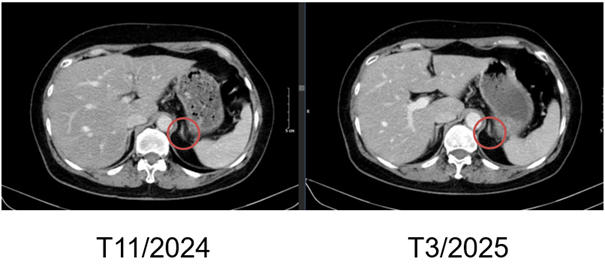

Hình 10. Hình ảnh chụp CT bụng trước và sau điều trị: Nốt tuyến thượng thận trái

– Chụp cắt lớp vi tính bụng: Theo dõi dày khu trú tuyến thượng thận trái tạo nốt đường kính khoảng 9mm (không thay đổi)

Hình 6. Hình ảnh chụp CT bụng sau điều trị: Nốt tuyến thượng thận trái